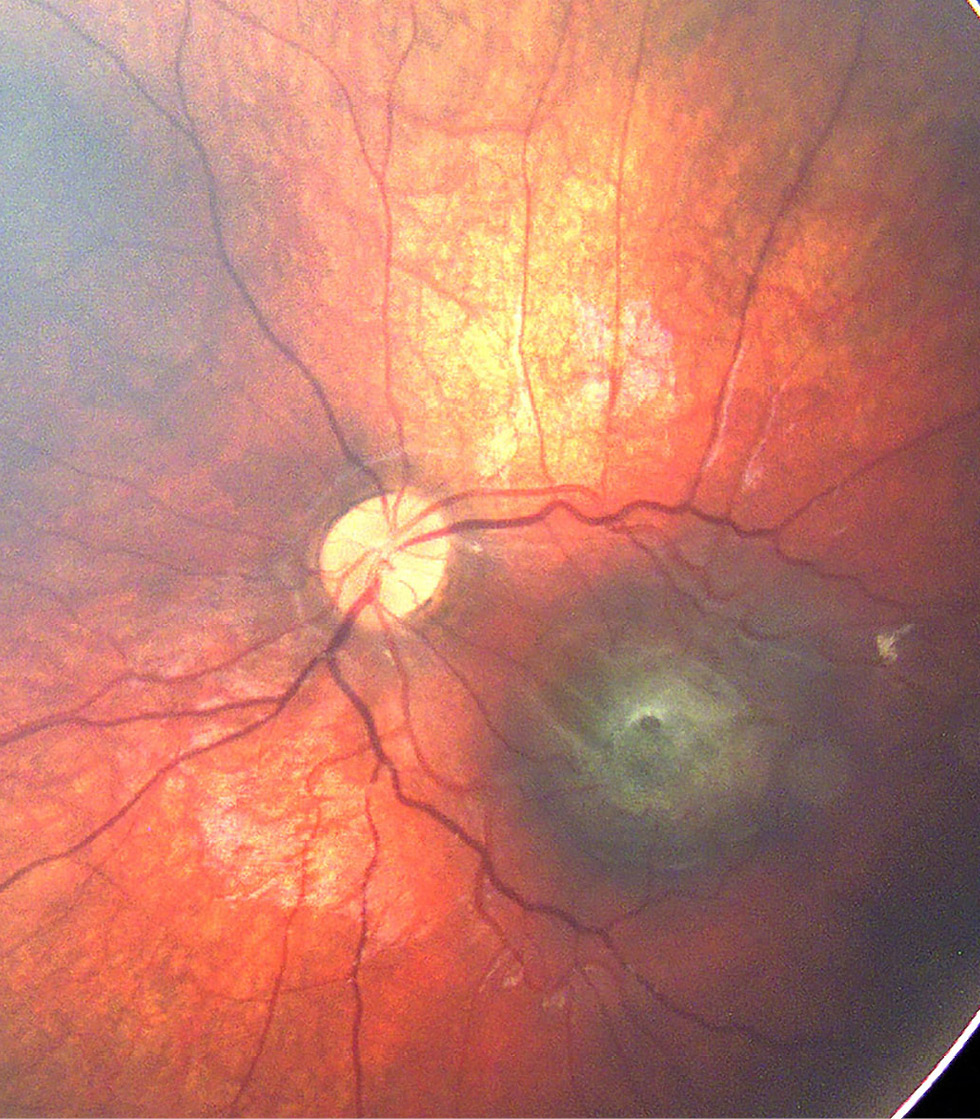

По данным ОКТ, максимальная толщина сетчатки в зоне гамартомы варьировала от 476 до 841 мкм (в среднем 691). ЭРМ определяли во всех случаях. Выраженный тракционный синдром, характеризующийся наличием складок сетчатки вследствие тангенциального натяжения, диагностирован у 10 детей [в 11 из 13 глаз с комбинированной гамартомой макулярной локализации (84,6%)] (рис. 2). В двух глазах с макулярной и перипапиллярной локализацией гамартомы отмечали незначительную тракцию сетчатки в центральной зоне со стороны ЭРМ (рис. 3).

Рис. 2. Оптическая когерентная томограмма сетчатки ребёнка 8 лет с комбинированной гамартомой сетчатки и ретинального пигментного эпителия: деформация витреоретинального профиля макулярной зоны, утолщение и дезорганизация слоёв сетчатки с формированием складок, эпиретинальная мембрана. Максимально корригированная острота зрения 0,15.

Fig. 2. Optical coherence tomography (OCT) of the retina in an 8-year-old child with combined hamartoma of the retina and retinal pigment epithelium: deformation of the vitreoretinal profile in the macular zone, thickening and disorganization of retinal layers with fold formation, epiretinal membrane. Best corrected visual acuity (BCVA) 0.15.

Рис. 8. Оптическая когерентная томограмма сетчатки ребёнка 11 лет с хориоидальной неоваскулярной мембраной, развившейся на фоне комбинированной гамартомы сетчатки и ретинального пигментного эпителия: деформация витреоретинального профиля макулярной зоны за счёт субретинального гиперрефлективного образования, перифокальная дезорганизация слоёв сетчатки. Максимально корригированная острота зрения 0,02.

Fig. 8. OCT of the retina in an 11-year-old child with choroidal neovascular membrane secondary to combined hamartoma of the retina and retinal pigment epithelium: deformation of the vitreoretinal profile in the macular zone due to a subretinal hyperreflective lesion, perifocal disorganization of retinal layers. Best corrected visual acuity 0.02.